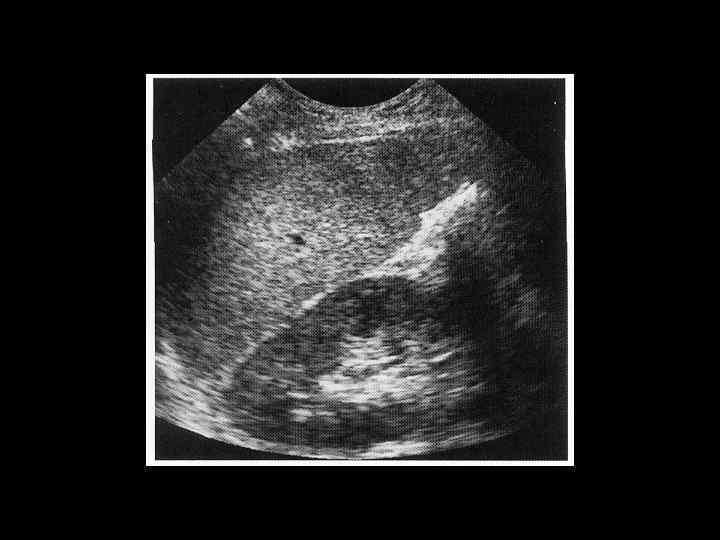

АКТУАЛЬНЫЕ ВОПРОСЫ РЕНТГЕНОЛОГИИ ЛУЧЕВАЯ ДИАГНОСТИКА ЗАБОЛЕВАНИЙ СЕЛЕЗЕНКИ Кисты и абсцессы селезенки